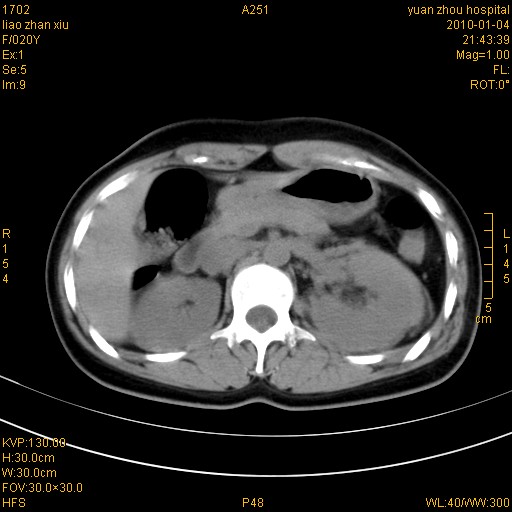

标题: CT23985:F20Y 外伤典型病例 [打印本页]

标题: CT23985:F20Y 外伤典型病例

左肾挫伤,包膜下积血。

左肾挫裂伤伴肾被膜下积血!另:肾周筋膜增厚!

1)左肾包膜下血肿。2)左侧肾挫伤可能;建议:行ct增强扫描检查。3)腰椎左侧横突骨折。

左肾挫伤,包膜下积血,l3、4左侧横突多发骨折。

双侧肾胞膜下出血,左侧较多。l3、4左侧横突多发骨折。

1、左肾挫伤,包膜下积血;

2、l3、4左侧横突多发骨折;

3、腹腔积气,考虑肠管破裂?

左肾挫伤,包膜下积血,L1、2、3、4左侧横突多发骨折。